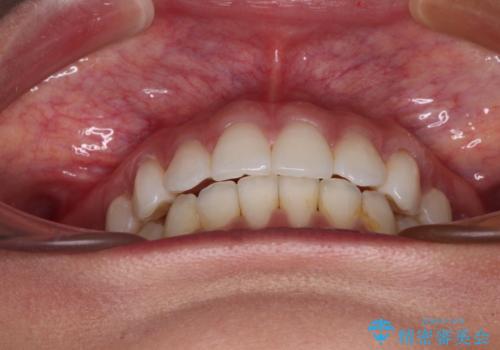

【モニター】インビザラインで口を閉じやすく

- 前に出ている上顎前歯が気になるとのことで来院された患者様です。

インビザラインを用い、IPR(歯と歯の間を削る)と歯列全体を後方に移動させることで、可能な限り前歯の突出感を改善することとしました。

元々の歯列も整っており、横顔の印象の出っ歯ではなかったため、仕上がりに満足できない可能性があると心配しておりましたが、口が閉じやすくなり、患者様には大変満足していただきました。